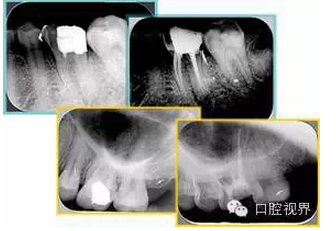

如圖為塑化加根充處理后牙齒 X 線片。

常見(jiàn)有修復(fù)性鈣化和增齡性鈣化。下面為根管鈣化 X 線片。

右圖及下圖為器械折斷的 X 線片。箭頭處示折斷器械。